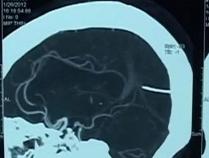

三歲男孩腹部凸起,醫生檢查發現在他的胃中居然有未成形的胎兒,也就是所謂的寄生雙胞胎。